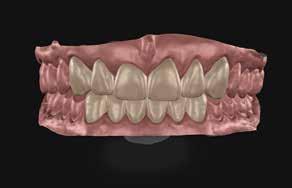

Behandlingsplan og behandling indbefatter IOS og sammenbid med leaf gauge, indtil posteriore kontakter ophæves, og der ses ca. 2 mm luft mellem molarer, svarende til ca. 4-5 mm plads i fronten. Der tages fotoserie og laves smiledesign i Smilecloud, som deles med teknikeren sammen med IOS. Teknikeren laver digitalt wax-up af 3,2,1+1,2,3 og 3,2,1-1,2,3 ud fra smiledesignet og tandlægens instruktioner. Herefter printes modeller og klare siliconestents til plastopbygning i overkæben (Fig. 8 A).

Underkæbefronten bygges op i fri hånd. Der anvendes kofferdam (Fig. 7 D, E, F, G). Vi anvender nanohybrid kompositplast

A1 (Venus® Diamond Kulzer, US) på alle slidflader posteriort samt palatinalt i overkæbefronten (Fig. 8 B, C). I det æstetiske område facialt på 3,2,1+1,2,3 og 3,2,1-1,2,3 anvendes dentin og emaljeflowplast (GC Essentia Light Dentin, Gaenial Flow samt Bleach White og GC Light Enamel, GC) (Fig. 8 D). I overkæbefronten bygges hver anden tand op ud fra stent. Dette gøres i Venus Diamond A1. Herefter laves facialt cut back og direkte layering med Light Dentin, tints og afsluttende Light Enamel (Fig. 8 C, D). Efter indslibning i okklusion og artikulation bygges tænderne op posteriort i fri hånd med overdækning af svækkede cuspides. Efter endelig justering af okklusion og artikulation (Fig. 8 E, F) samt polering til efterfølgende kontroller (Fig. 8 G, H) fremstilles hård bidskinne med fuld balanceret kontakt til natlig brug.